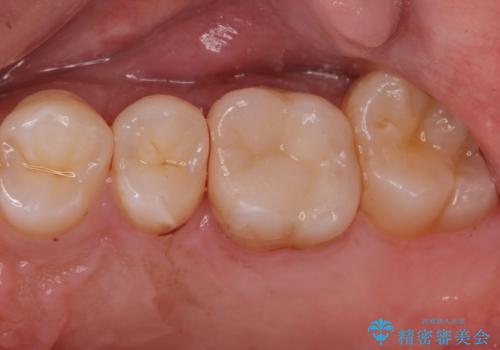

- 金属アレルギーが気になるとの事で来院。

拡大鏡下で銀歯を外し、セラミックの詰め物で修復しました。